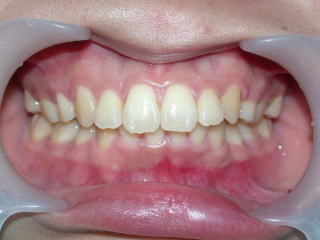

術前術後

2022年7月→2024年5月(2年弱でした。これから保定期間に入ります。)